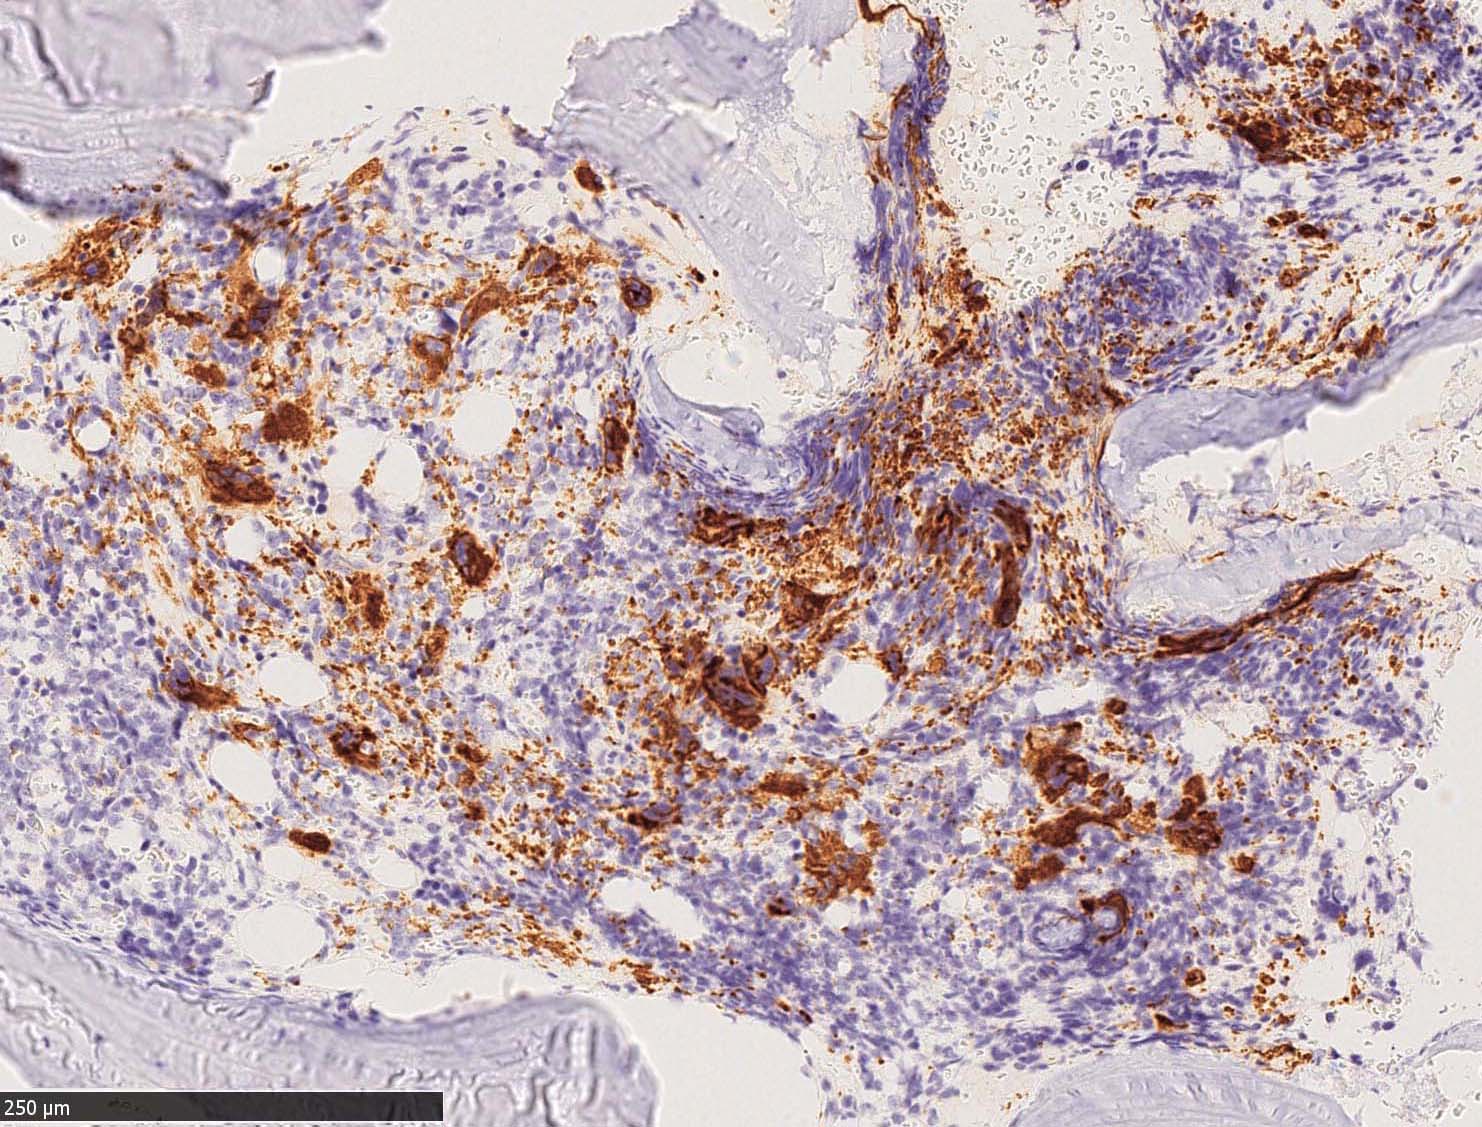

CD42b染色